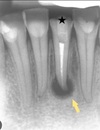

# 20. Chronic periodontitis. Etiology, classification, clinical features Chronis periodontitis classifications

* Periodontitis periapicalis **chronica** **granulomatosa** **diffuse** (**sin**/**cum** **fistulae**) * Periodontitis periapicalis chronica **granulomatosa** **localisata** * Periodontitis periapicalis chronica **fibrosa** * Periodontitis **chronica** **exacerba**

160

# 20. Chronic periodontitis. Etiology, classification, clinical features Characteristics of Chronic periodontitis

* Can occur w/ **low virulence mo** and **good immune status** * **Long course**-months/years * **Proliferation**->Blood vessels+tissues * **Fibrosis** of connective tissue

161

# 20. Chronic periodontitis. Etiology, classification, clinical features Periodontitis periapicalis chronica granulomatosa (sin/cum fistula) characteristics | Chronic granulating periapical periodontitis

* **Chronic purulent proliferative** process in bone * Bone **resorption** * **No** subjective complaints/pain * **Fistula** that may be located away from causative tooth * **Acute exacerbations** may occur- **painful, edema** and **hyperaemia**

162

# 20. Chronic periodontitis. Etiology, classification, clinical features Treatment of Periodontitis periapicalis chronica granulomatosa (sin/cum fistula) | Chronic granulating periapical periodontitis

* Endo * Tooth extraction * Resection of root tip * Hemisection * Anti-inflammatory treatment-osteotrophic drugs ##Footnote -Osteotrophic drugs=>modify bone metabolism by inhibiting bone resorption or stimulating bone formation=> -Bisphosphonates(inhibit bone breakdown) -RANKL inhibitors(Denosumab) -Parathyroid hormone analogues(bone formation stimulators)

163

# 20. Chronic periodontitis. Etiology, classification, clinical features Periodontitis periapicalis chronica granulomatosa localisata characteristics ## Footnote Chronic periapical granulomatous localisaed periodontitis

* **Necrosis** and **bone destruction** replaced by **granulation tissue=>** * Granulation tissue formation followed by **fibrosis** w/ proper treatment and optimal response=> * Becomes **granuloma** w/ **inadequate** treatment or poor response

164

# 20. Chronic periodontitis. Etiology, classification, clinical features Granulation tissue cells

* Well vascularised and rich in cells * Fibroblasts * Endothelial cells * Plasma cells * Mast cells

165

# 20. Chronic periodontitis. Etiology, classification, clinical features Granuloma characteristics

* **Chronic inflammatory response**=> Granulation tissue rich in **cells** and **blood vessels** * **Connective tissue capsule=>**limits penetration of infection

166

# 20. Chronic periodontitis. Etiology, classification, clinical features Types of Granuloma according to their histology

* **Common** Granuloma/granuloma simplex * **Epithelialising** granuloma * **Cystic** granuloma/Granuloma cycsticum

167

# 20. Chronic periodontitis. Etiology, classification, clinical features Treatment of granuloma

* Extraction * Endo * Surgical removal of granuloma * Hemisection of roots * Less common-reimplantation and autotransplantation of root

168

# 20. Chronic periodontitis. Etiology, classification, clinical features Periodontitis periapicalis chronica fibrosa characteristics

* **Following** **endo** treatment * Granulation tissue **replaced** w/ fibrous tissue * **Reduction** in cells and vessels- w/exception of **fibroblasts** * Fibrous tissue **replaced** w/ **bone** after some months ## Footnote Healing phase of acute and chronic periodontitis

169

# 20. Chronic periodontitis. Etiology, classification, clinical features Treatment of chronic periodontitis

* **Extraction**-Followed by **removal /curettage** of pathologically altered tissue/granuloma * **Endo-rare** * **Surgical** methods

170

# 20. Chronic periodontitis. Etiology, classification, clinical features Surgical methods of treatment of Chronic Periodontitis

* Apical osteotomy * Hemisection * Amputation * Reimplantation * Autotransplantation * Coronory radicular seperation

171